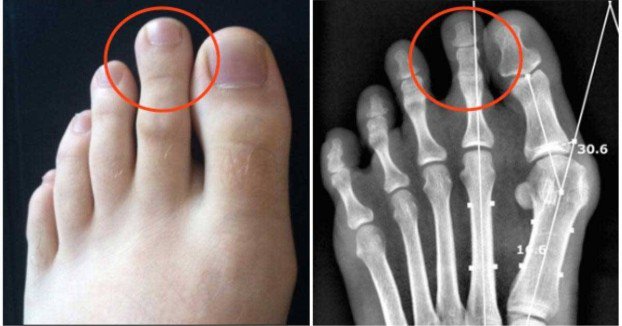

Ovo vam je sigurno privuklo pažnju, makar sa gledišta estetike! Radi se o tzv. Grčkom stopalu, pri kojem je drugi nožni prst duži od prvog i javlja se kod svega 14% stanovništva.

Iako nekim ljudima izgleda ružno i najradije bi željeli da ga nemaju, grčko stopalo obično je povezano sa snagom, inteligencijom i seksipilom. S druge strane, postoje neke okolnosti koje bi trebalo uzeti u obzir.